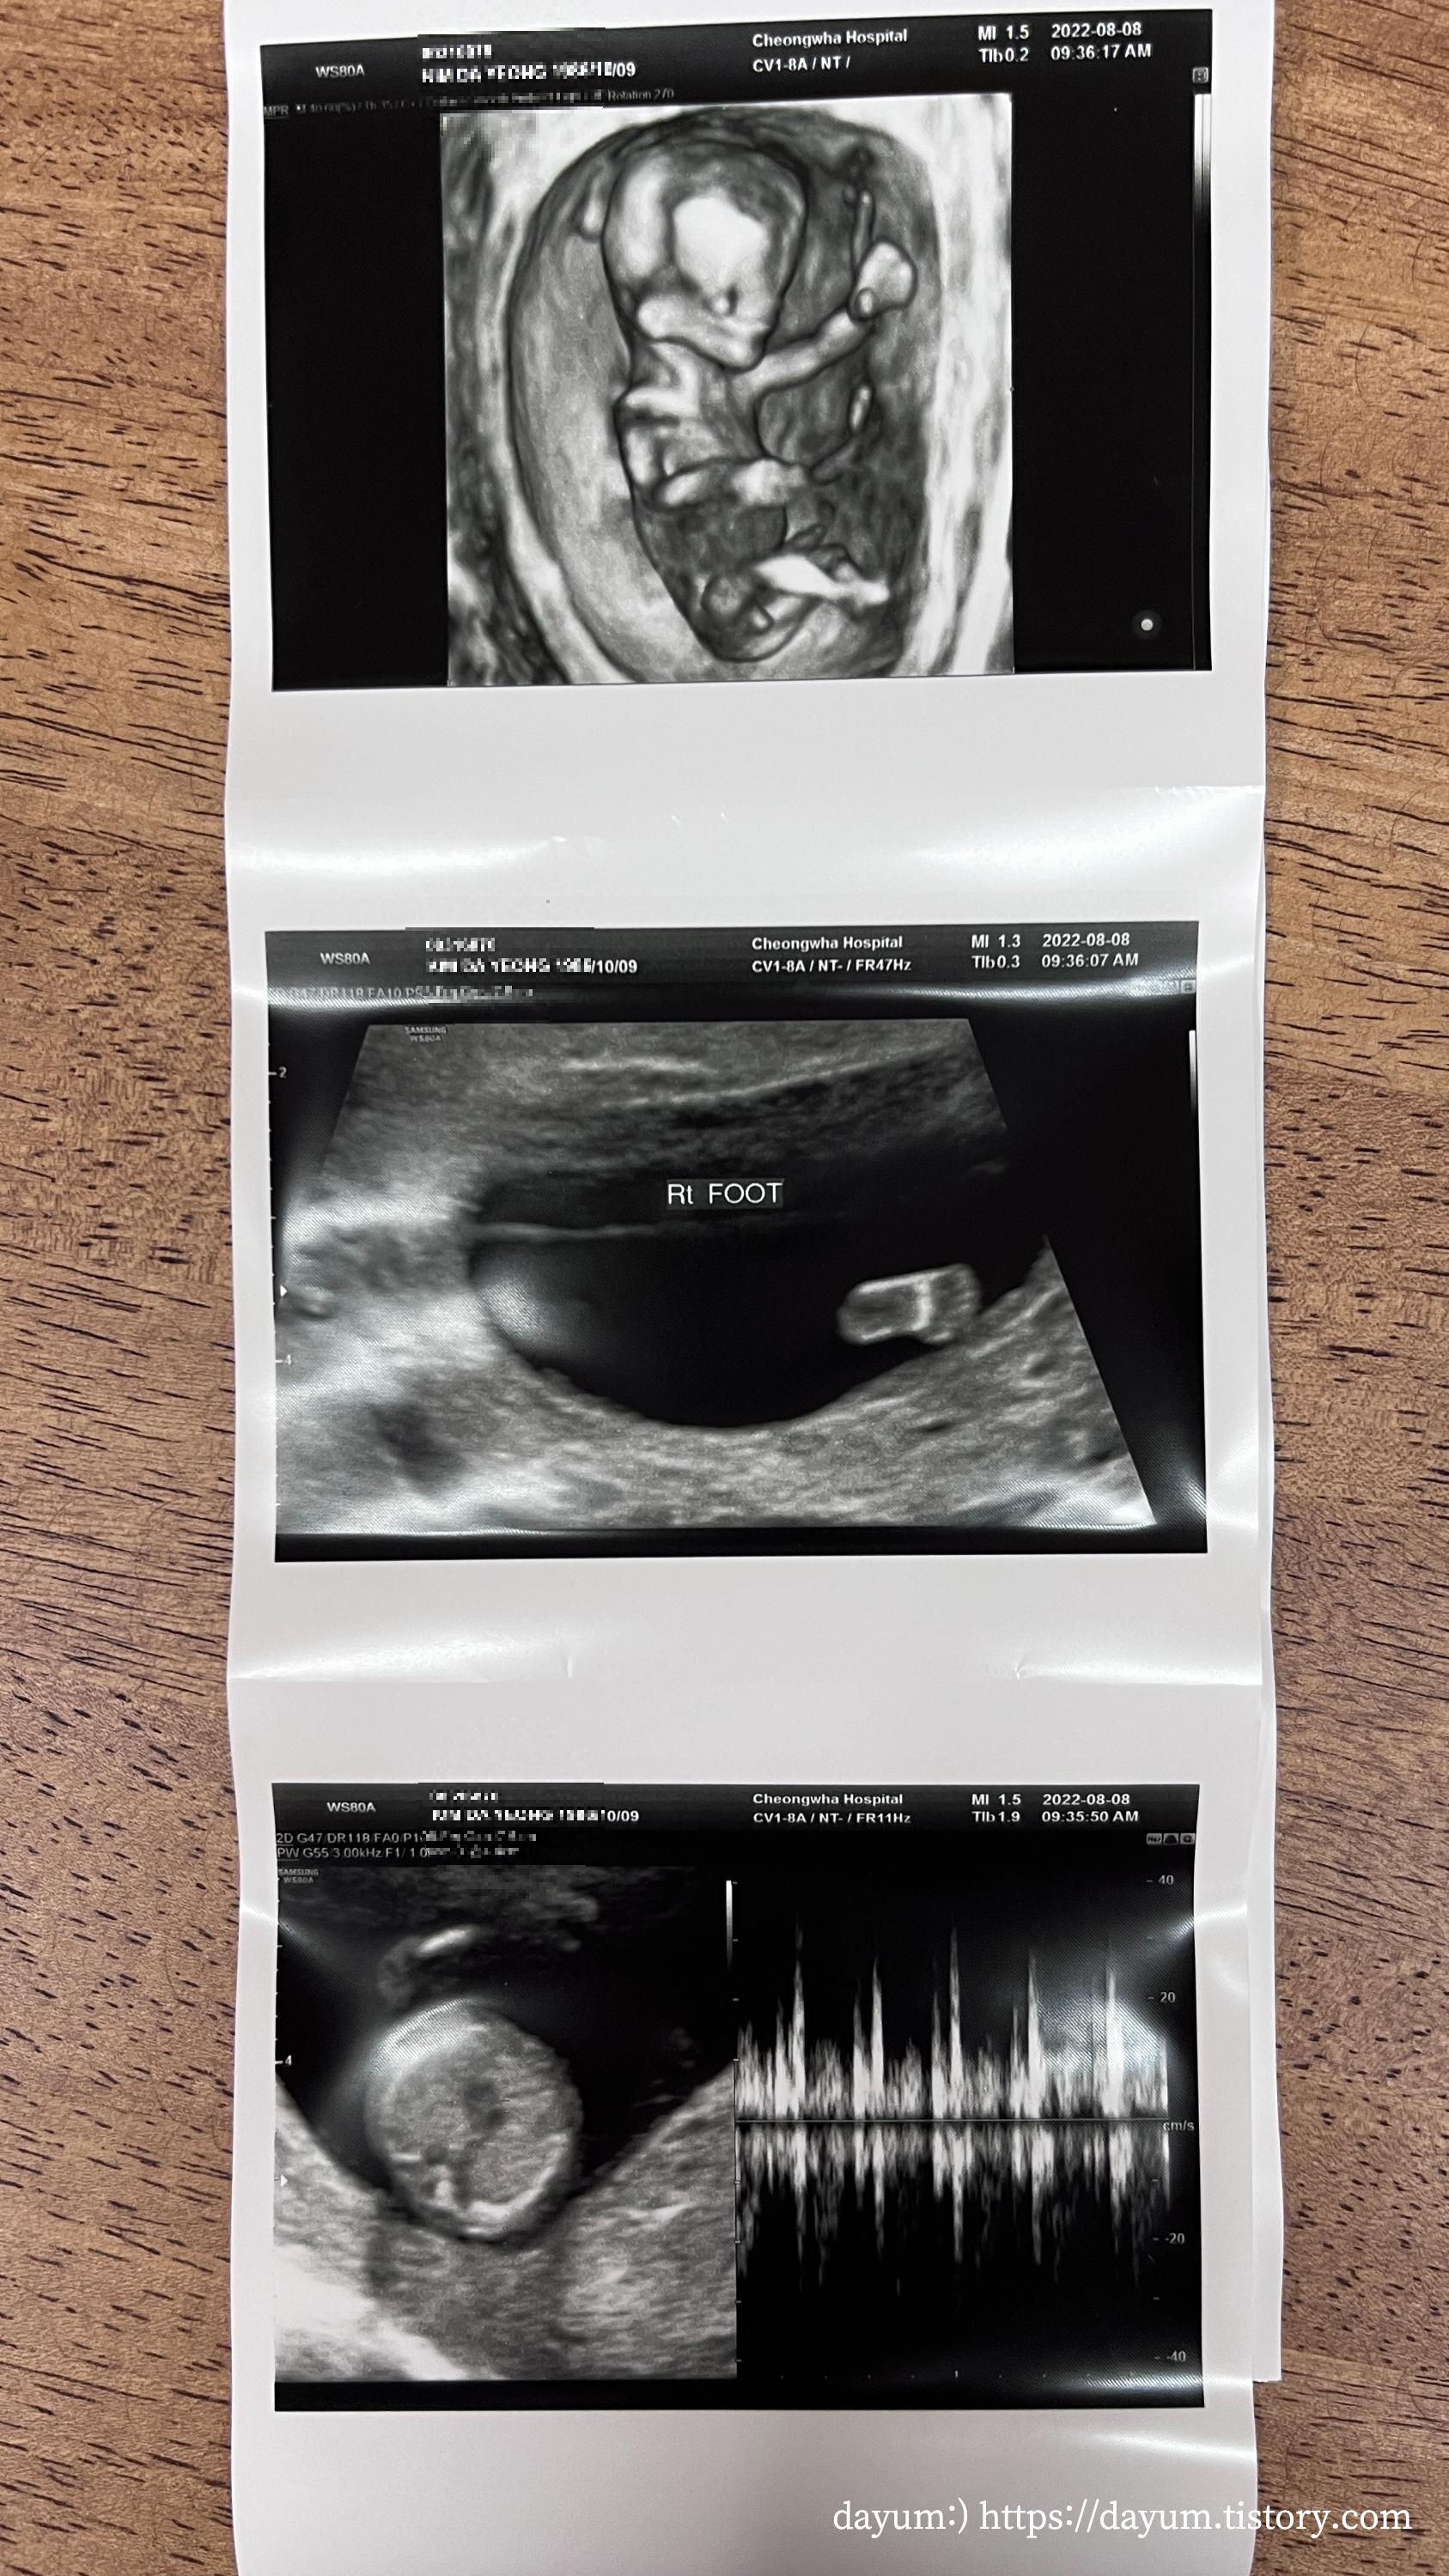

입체초음파는 태아가 협조를 잘 해줘야 금방 끝난다고 했는데 조이는 잘 자고 있다가 끝날 때 쯤 일어나서 약 7분만에 끝났다.

생각보다 배꼽 아래에 있었는데, 두다리를 꼬고 있고, 한쪽 팔로 가드를 치고 있었다.

태아의 뇌는 나비모양으로 잘 형성되었고, 코뼈, 상악, 하악 모두 잘 만들어졌다고 한다.

탯줄로 혈액이 공급되는 것도 봤고 목투명대는 1.31mm로 정상범위에 있다고 한다.

오른쪽 발바닥이 초음파에 잘 찍혀서 오늘의 포토로 뽑아주셨다. ㅋㅋ 귀여워 -